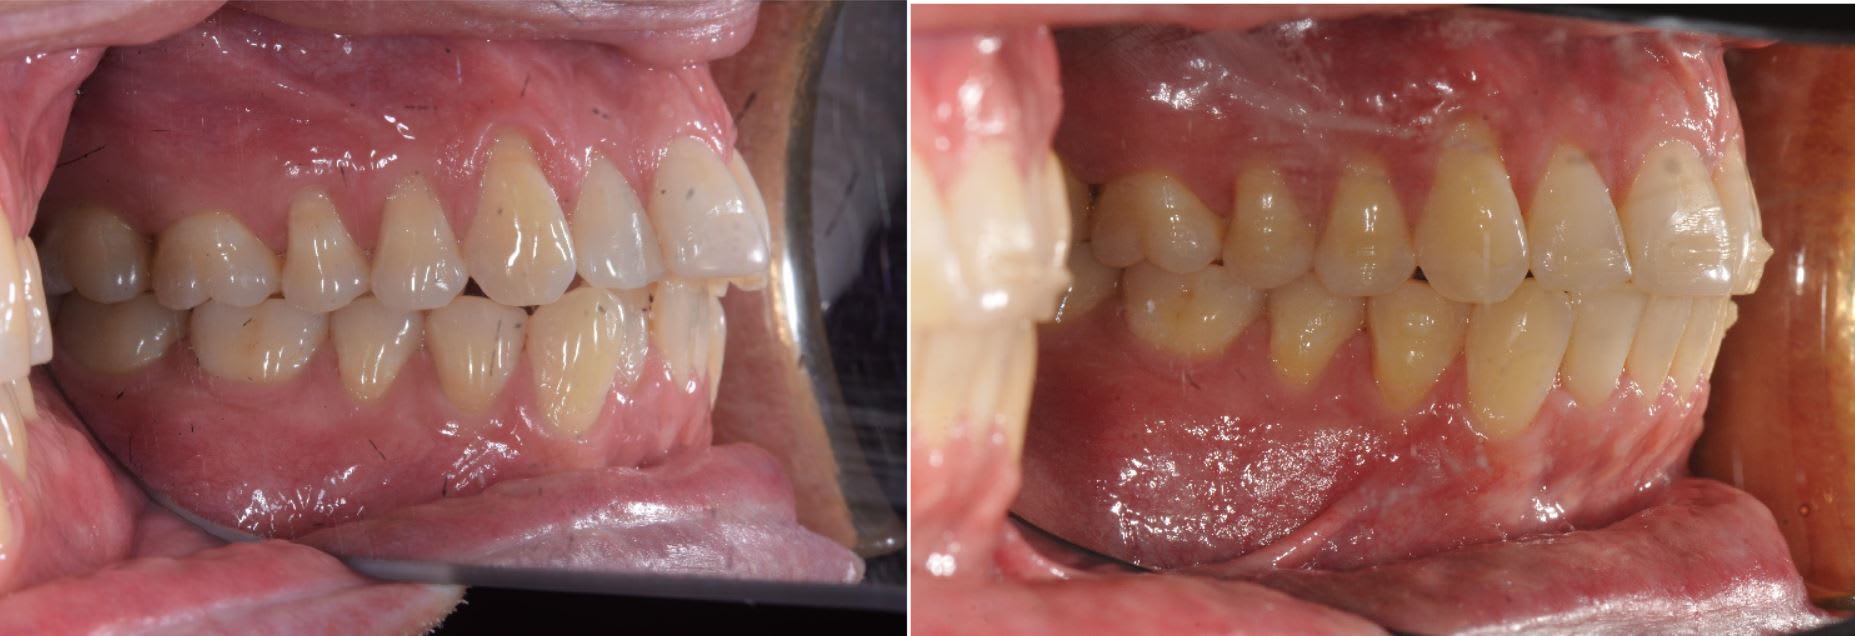

Un bon exemple d'utilisation aligneur maison en orthodontie.

On à commencé avec de la 2D pendant quatre mois, puis trois mois avec aligneur.

Là c'est un exemple classique d'une utilisation qui devient très intéressante quand vous faite in-house car ça permet d'être très réactif ( aligneur près en deux jours ).

Le patient ne venait que pour de brève durée sur Phnom Penh, donc pas possible d'avoir les gouttières à temps en passant par un lab extérieur.